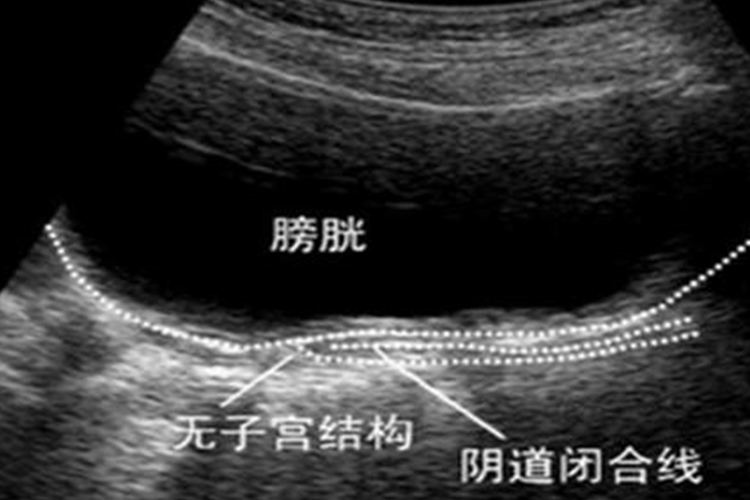

盆腔B超:为首要的诊断方法。B超检查常显示子宫缺如,或膀胱顶部后方可探及一实性小结节,即为始基子宫。对于少数有功能内膜但发育不良子宫的患者可显示为盆腔包块或积血的子宫,卵巢一般显示为正常大小。